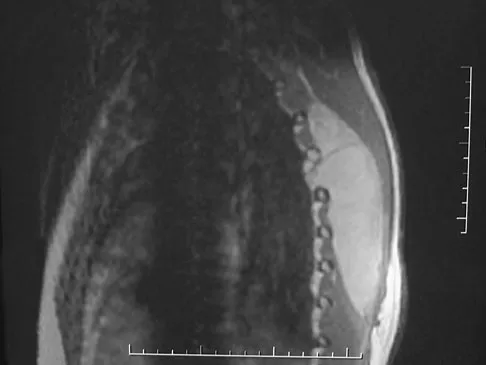

A 25-year-old man has chronic back pain that has been slowly worsening. He has no constitutional symptoms, and he denies any previous medical problems. Examination shows a tall lean build with no objective neurologic findings or skin lesions. Figure 32 shows a T2-weighted sagittal MRI scan. What is the most likely diagnosis?

Explanation